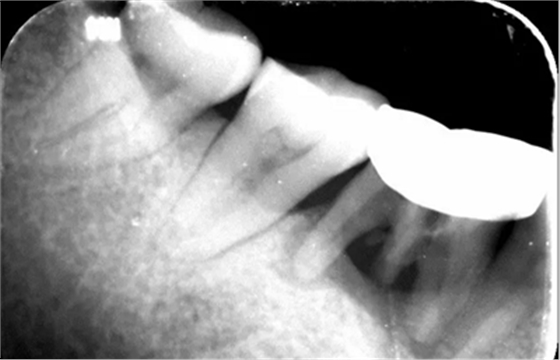

4、术前根尖片